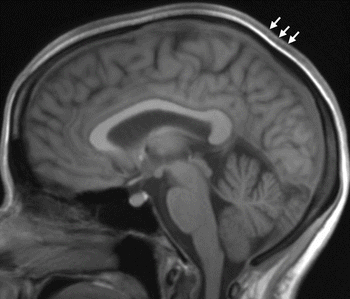

Astronauts experience a sustained increase in brain volume and other impacts.

CT and MRI scans show neurological impacts.